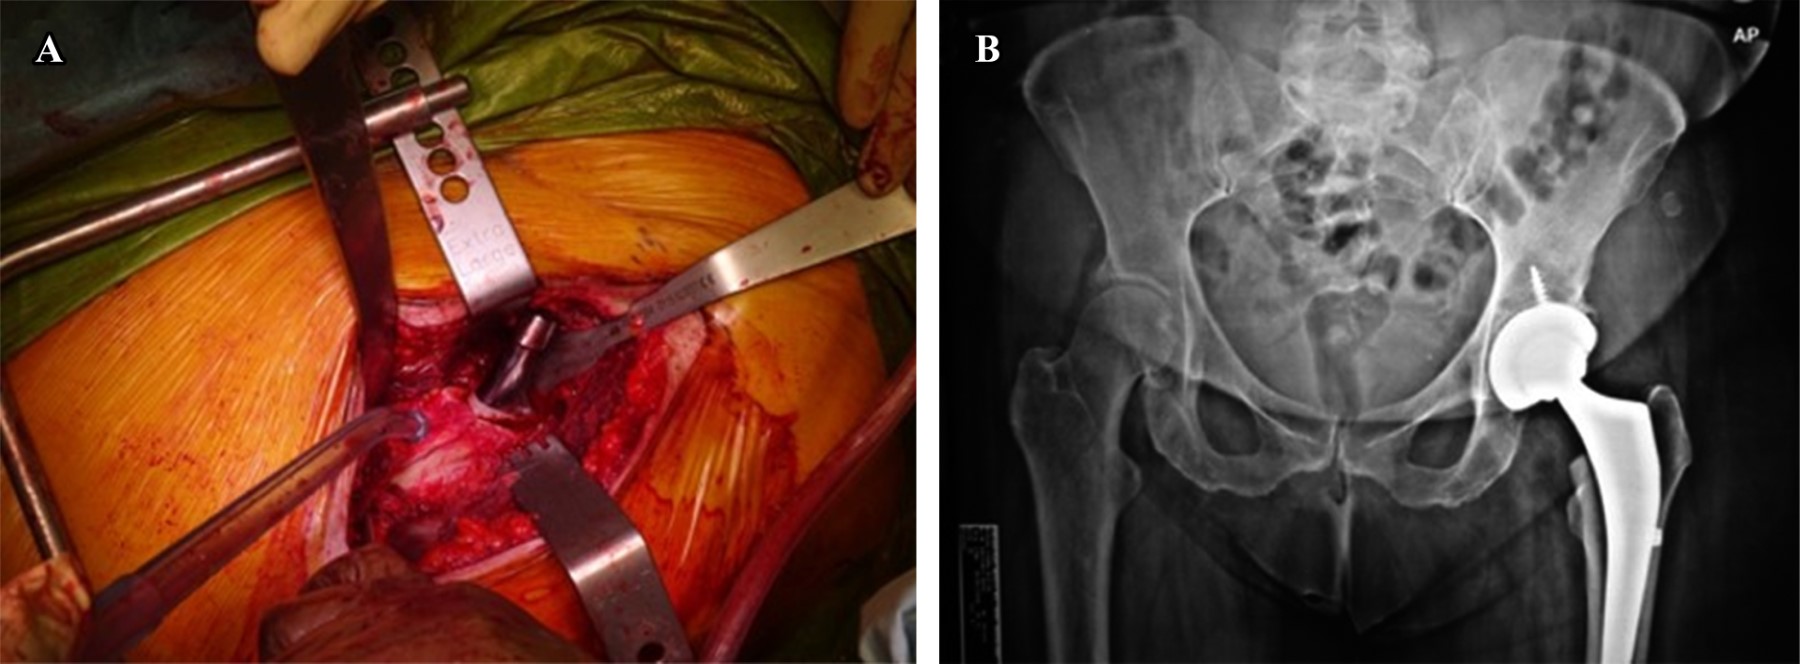

The incision begins 2 cm distal and 3 cm lateral to the anterosuperior iliac spine and continues obliquely between 8 and 10 cm distal and slightly laterally, over half of the palpable muscle mass of the tensor fascia lata (TFL) (Figure 1), the skin is at risk during surgery, this is the most encountered minor complication either by excessive traction of the automatic retractors or by the superficial introduction of the broaches. In overweight, elderly, and/or patients with great quadriceps muscles, the incision should be adjusted to the surgeon's requirements initially to avoid injuring the dermis. An obese patient who has an overhanging fat apron will have poorer skin in the proximal part of the wound, which leaves the wound at risk of being under the fold or even folded over itself when the patient adopts a sitting or upright position postoperatively, is why the authors' prefer to adjust the incision slightly curved posteriorly in the proximal part in this type of patient, and do not cross the inguinal crease.8,9

MUSCLE INJURY

Soft tissue retraction is necessary for the correct visualization of the structures for THA. As a result, incorrect placement of retractors, wrong direction, or overzealous retraction may cause shearing damage to the TFL, rectus femoris (RF), or both. This can be avoided by utilizing specialized retractors (deep blades with curved sides) developed for minimal-incision surgery, meticulous attention to the placement of retractors, and the force and direction of retraction. If performed carefully, minimal damage to both muscles will occur with routine exposure to the DAA THA.

The author's preferred retractor is the Beckman-Adson, used solely in most surgeries and is placed parallel to the fibers of the TFL and RF. For obese and muscular patients, we utilize a modified Charnley hip retractor for its deeper blades, protecting the TFL belly muscle with gauze between the retractor and the muscle.12

As for capsular exposure, several authors prefer a referred capsulotomy, sometimes involving releasing the reflected head of the rectus femoris to improve exposure. This way, the capsulotomy between the retractor and the muscle belly can also be used. Special sets of various retractors have been developed for acetabular exposure.13